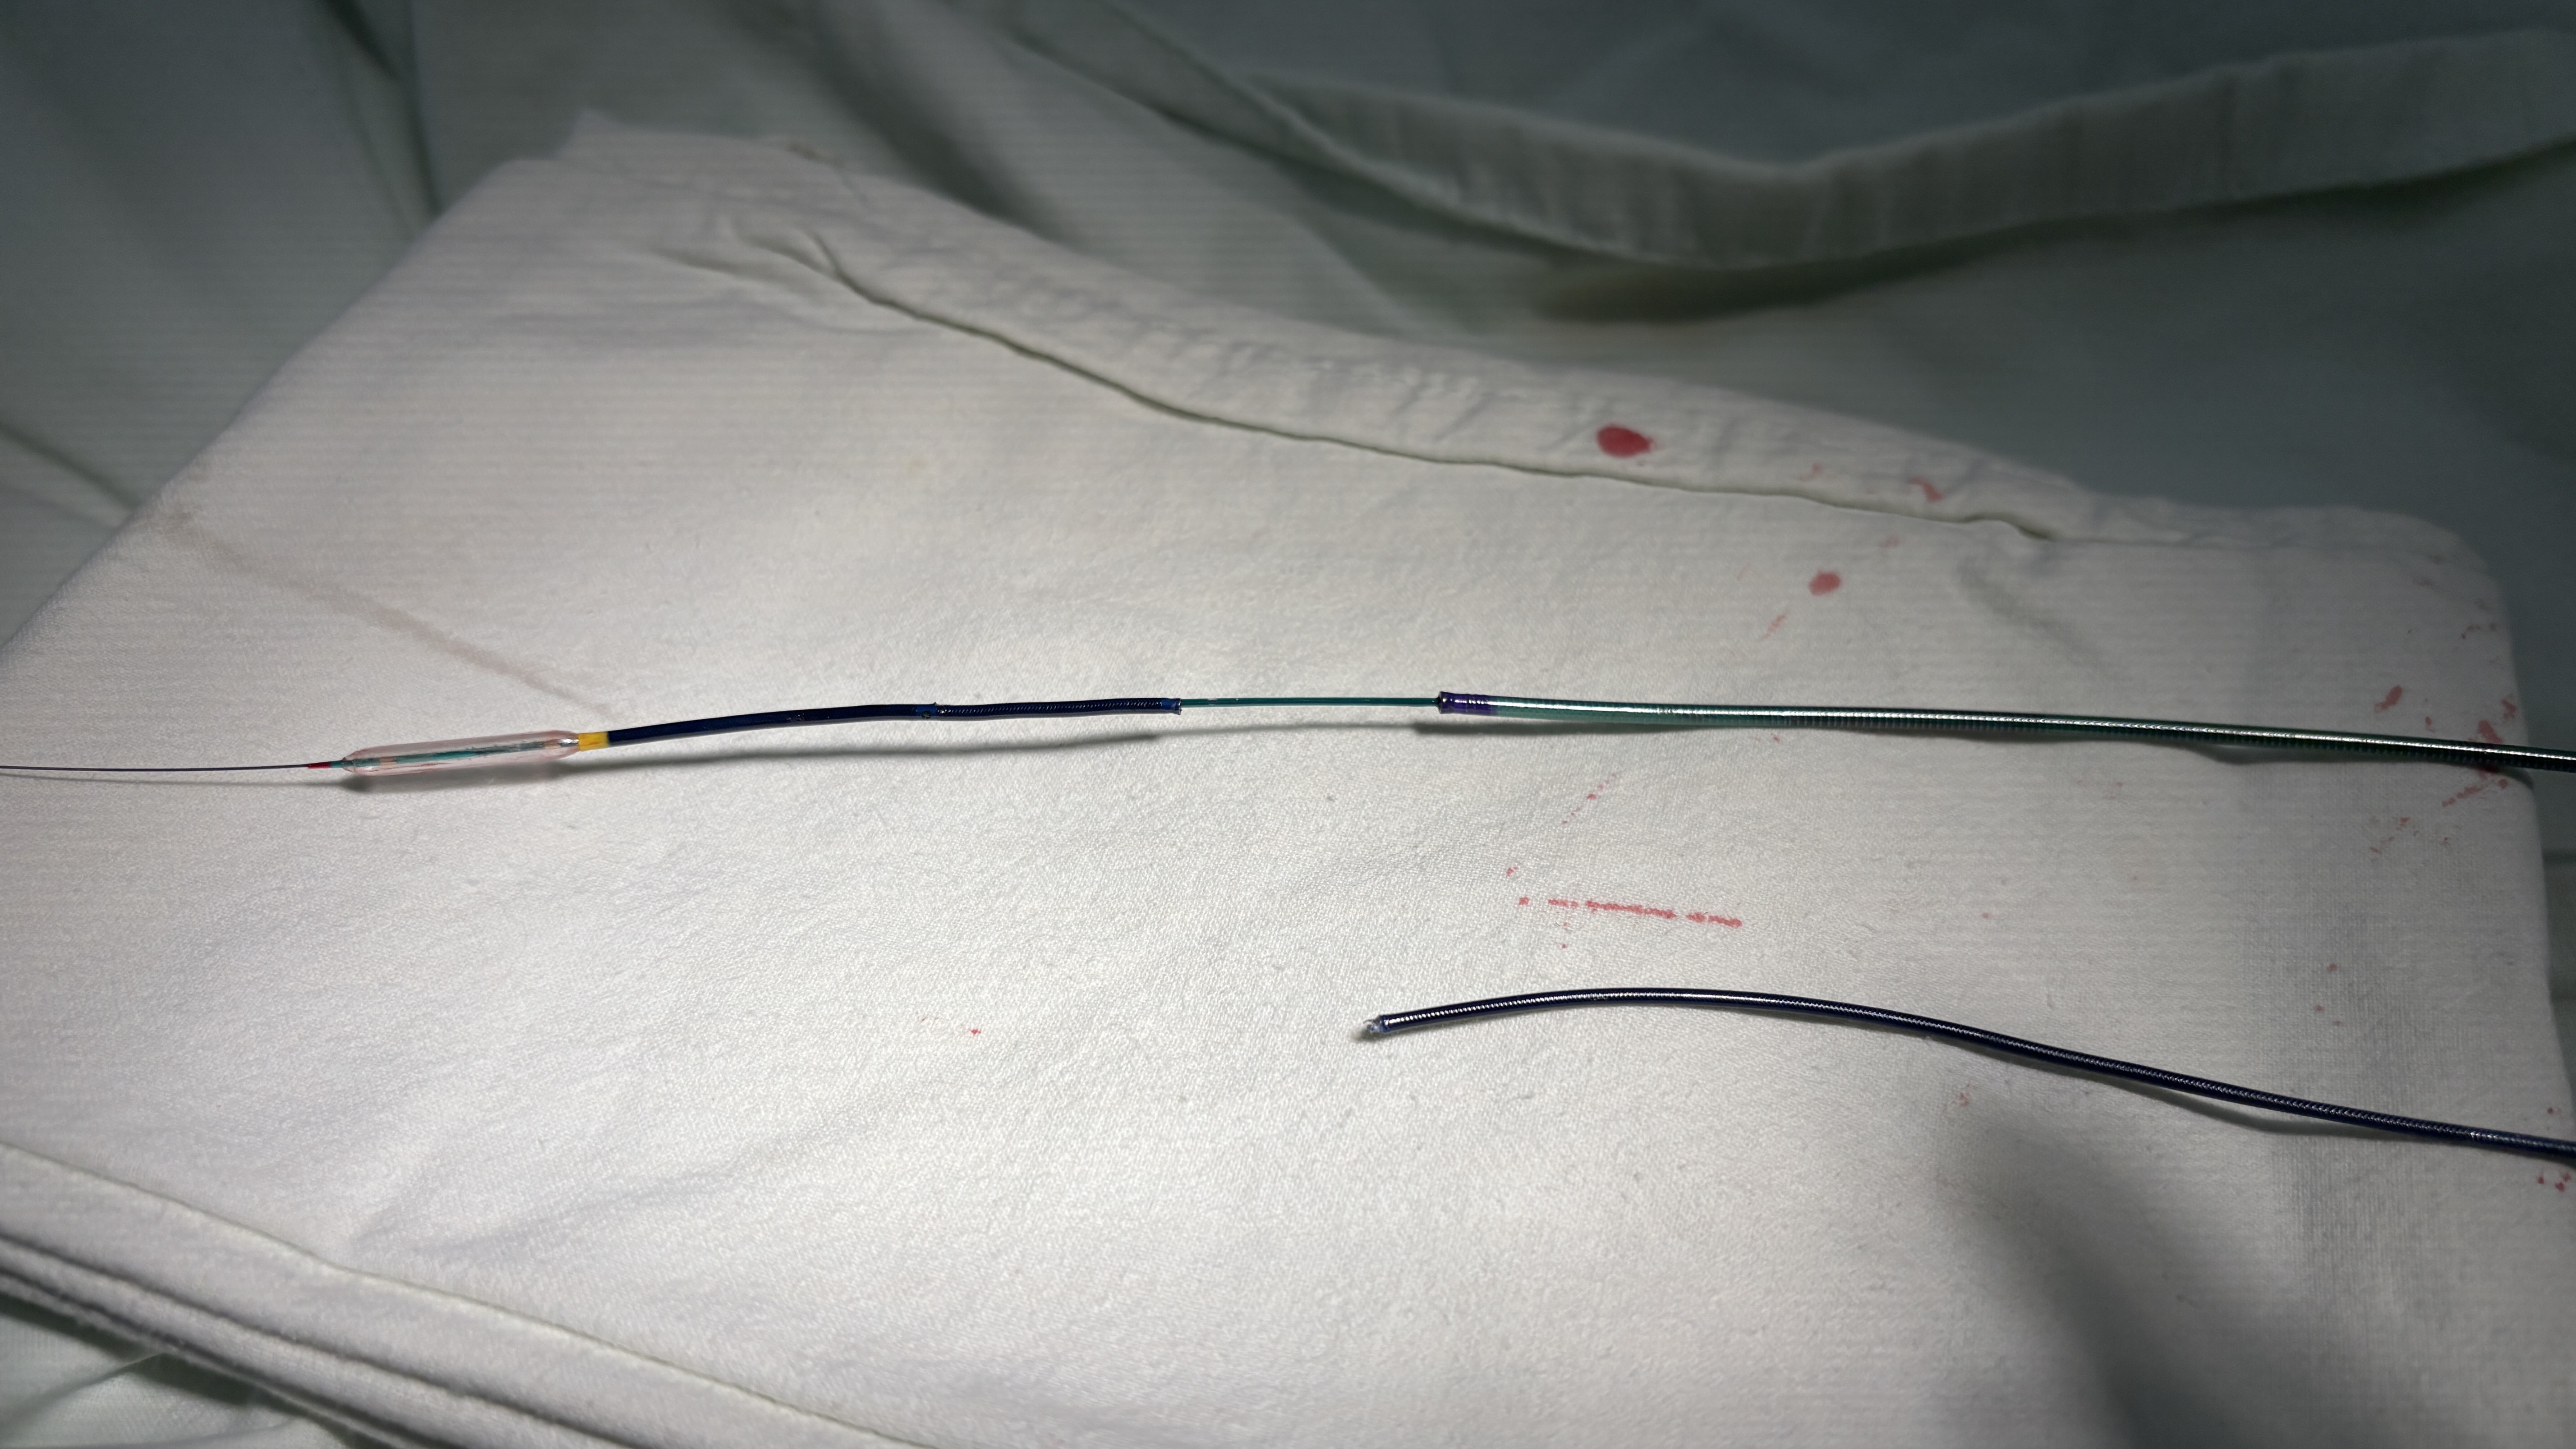

A 3.5x7F ASAHI PB Guide catheter with Sion guidewire was provided for LAD revisualization.After placing the guidewire in LAD, series balloon were provided todilate the stenotic lesions as Figure 1 showed. A 2.5x38 mm stentwas applied to place the distal part lesion of LAD. However, the difficulty to movethe stent to the correct place due to length of the stent and the irregularlumen of proximal part of LAD. 6.0F extension microcatheter was used to assistthe stent moving and implanting. After stenting, the extension microcatheterwas entrapped around middle part of LAD as Figure 2 showed. After pullingbackwards forcedly, the fracture of proximal part of the microcatheter was detectedand previous guidewire was pull out from coronary artery. After rewiring into the distalpart of LAD via the lumen of the fractured microcatheter, 7.0F telescopemicrocatheter with a 2.5x15 mm balloon was applied. The balloon wasmoved in the position 2-3 mm inferior to the fractured microcatheter and proximalpart of telescopemicrocatheter was placed in the ostium of left main coronary artery. After theballoon inflated, the whole sets including the body of the balloon and thetelescope microcatheter were pull backwards. The fractured catheter was movedbackwards with the inflated balloon to enter the telescope microcatheter. Thewhole sets with the fractured catheter were retried from the patientsuccessfully. The retried balloon and fractured catheter were illustrated inFigure 3.